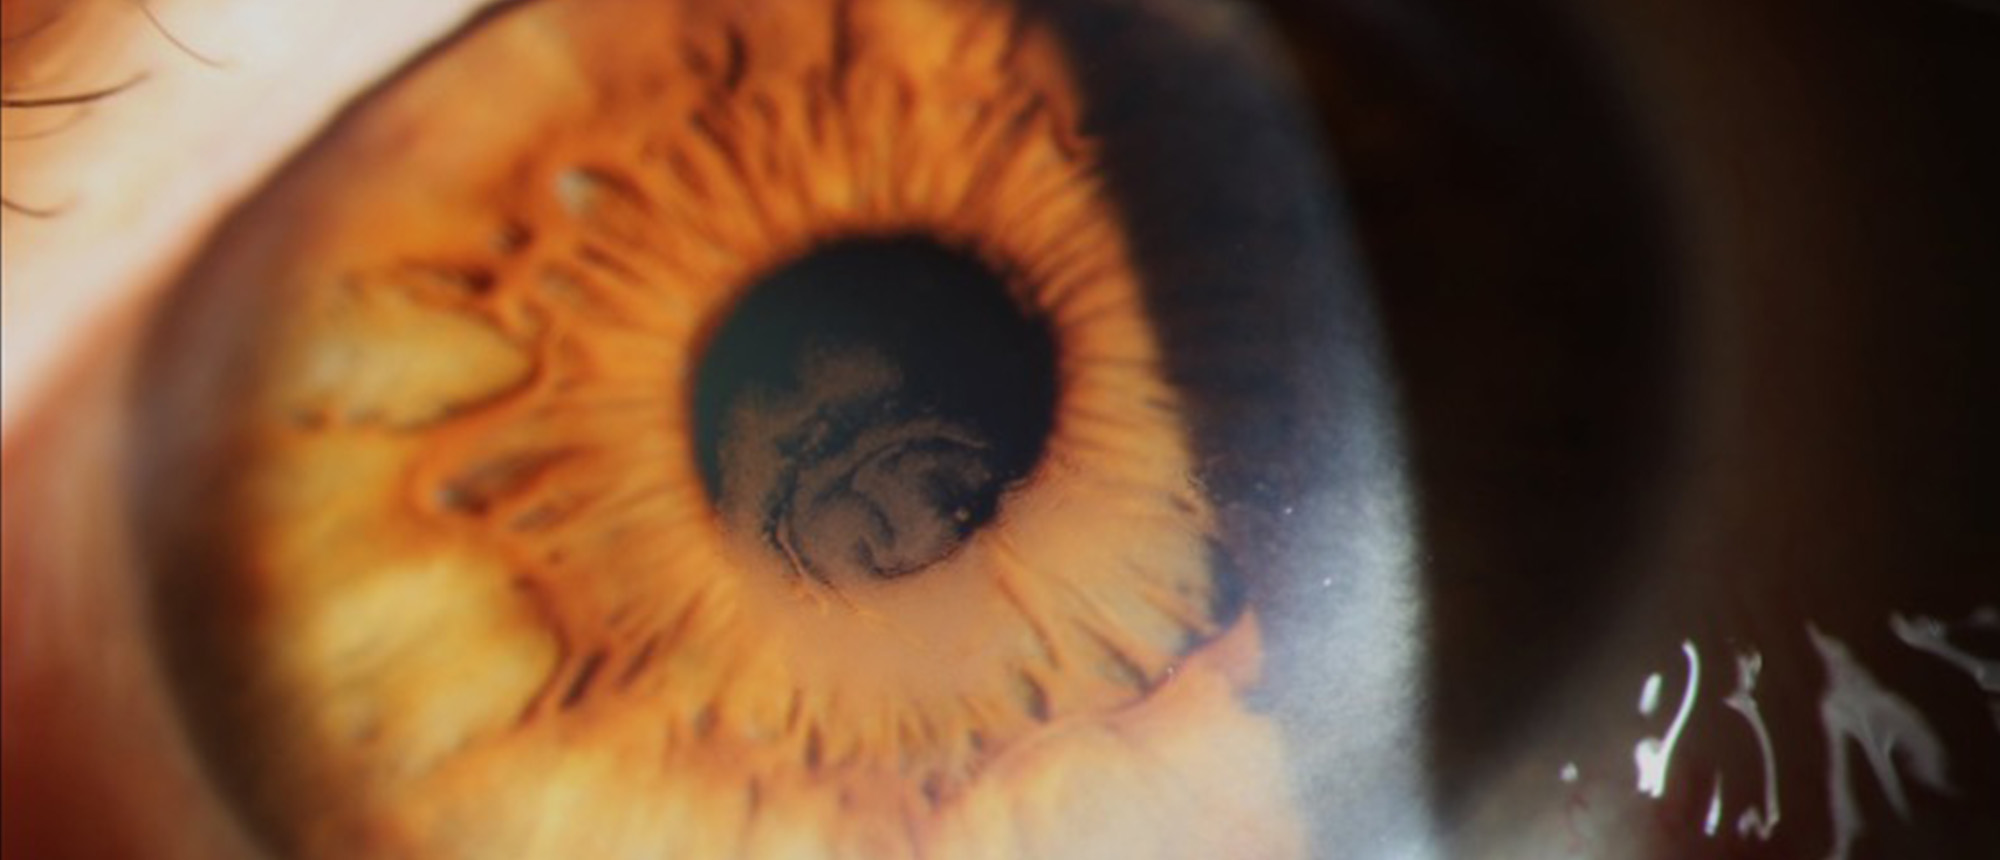

Nontuberculous Mycobacteria Keratitis A patient five months after bilateral simultaneous cataract surgery in another country presents to the BPEI emergency room with bilateral decreased vision and extreme right eye pain for the last 2 weeks. Their exam was notable for visual acuity of hand motion i…